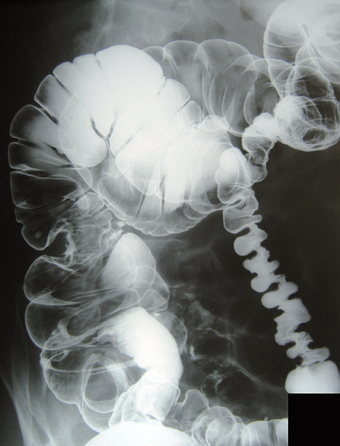

②注腸検査

肛門から造影剤(バリウム)を注入してX線撮影を行う検査です。大腸全体の形状を見て病変の位置・大きさ・大腸が一部で狭くなっていないかなどを確認します。この検査も前日昼から食事制限を行い夜は下剤を服用し便を出します。この検査で異常所見が見つかった場合には、次に大腸内視鏡検査を行うことになるため、当院では精密検査としては最初から大腸内視鏡検査を行うことがほとんどです。注腸検査では大腸内視鏡検査に比べて検査精度が低く、平坦な早期がんは部位によっては見つからない場合があり、S状結腸などでは進行がんがあっても見つかりにくい場合もあります。ただ内視鏡がどうしても挿入できない場合や手術前の検査として癌の場所を確認する目的などでは注腸検査が必要になります。